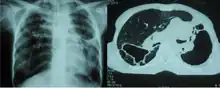

| Fibrothorax caused by infection with M lentiflavum. | |